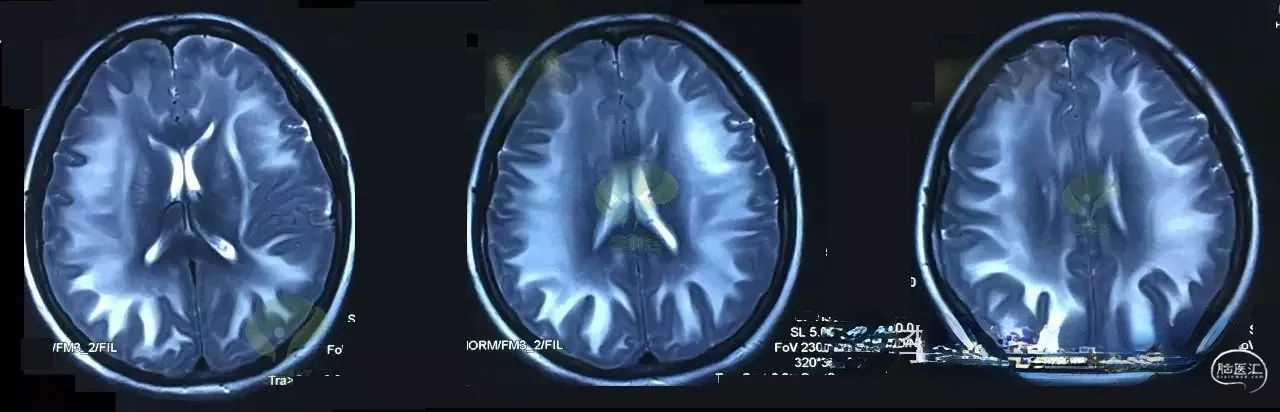

有了现代化的医学成像技术,医生才真的算是能够看到“病”,看到了脑内血肿、脑梗塞、脑血管狭窄和广闭塞等等。根据影像结果,更加准确地对病人的病情进行判断。

选择什么样的检查项目,也能体现出一位医生的知识、水平、经验和是否有责任心。比如磁共振,有十多种参数,上百个序列,不可能对患者进行所有项目的检查,如何选择使用这些序列,就不是一朝一夕的努力所能达到的。如诊断超早期脑梗塞,选择DWI,排除脑出血,选择SWI,诊断脑室旁病灶,选择FLAIR,鉴别诊断急性脑梗塞和多发性硬化,选择T1WI、T2WI和DWI等等。因此,检查设备再先进,也离不开临床医生的基本功。